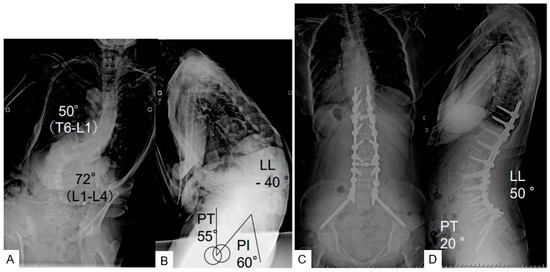

| LL (degree) | 8.8 ± 18.4 | 50.1 ± 9.3 | p < 0.01 |

| PT (degree) | 35.5 ± 9.3 | 14.1 ± 8.8 | p < 0.01 |

| PI (degree) | 49.9 ± 10.2 | 50.1 ± 10.4 | p < 0.01 |

| PI-LL (degree) | 41.1 ± 19.6 | 0.35 ± 11.1 | p < 0.01 |